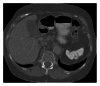

Spleen can have a wide range of anomalies including its shape, location, number, and size. Although most of these anomalies are congenital, there are also acquired types. Congenital anomalies affecting the shape of spleen are lobulations, notches, and clefts; the fusion and location anomalies of spleen are accessory spleen, splenopancreatic fusion, and wandering spleen; polysplenia can be associated with a syndrome. Splenosis and small spleen are acquired anomalies which are caused by trauma and sickle cell disease, respectively. These anomalies can be detected easily by using different imaging modalities including ultrasonography, computed tomography, magnetic resonance imaging, and also Tc-99m scintigraphy. In this pictorial essay, we review the imaging findings of these anomalies which can cause diagnostic pitfalls and be interpreted as pathologic processes.